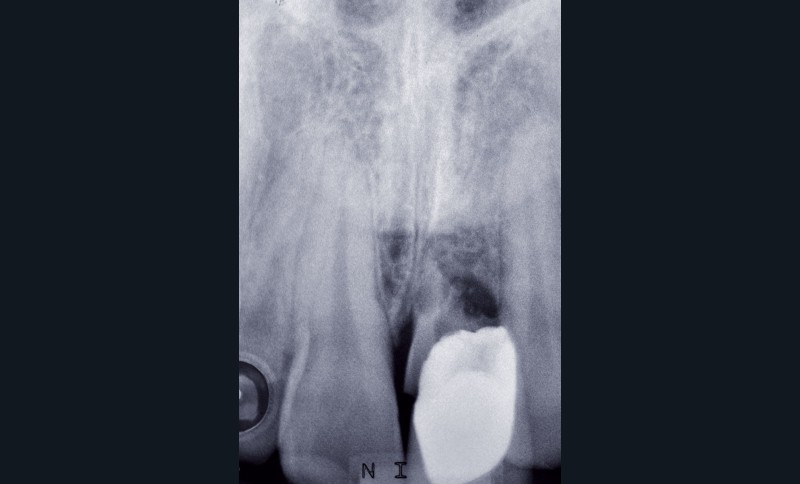

L’examen radiographique permet d’observer l’étendue de la résorption radiculaire (fig. 4).